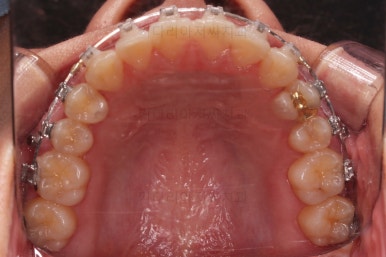

윗니의 배열과 위치는 거의 완성이 되었고요.

아래는 아직 틈이 많이 보이죠.

어금니를 부산치아교정 통해 계속 앞으로 당겨줍니다.

아랫니 틈은 거의 없어졌네요.

대신 여러 교합적인 이유로 아랫니를 좀 더 앞으로 당겨주긴 해야 합니다.

이제 마무리를 해봅니다.

교합 양호하고 치아 사이 틈새도 잘 모아졌습니다.